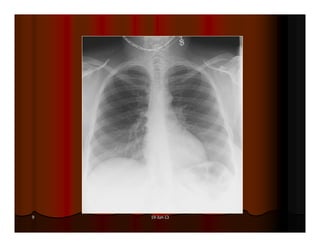

AÙP-XE THUØY TREÂN PHOÅI (P)

June 19, 2013 AÙP-XETHUØY TREÂN PHOÅI (P)